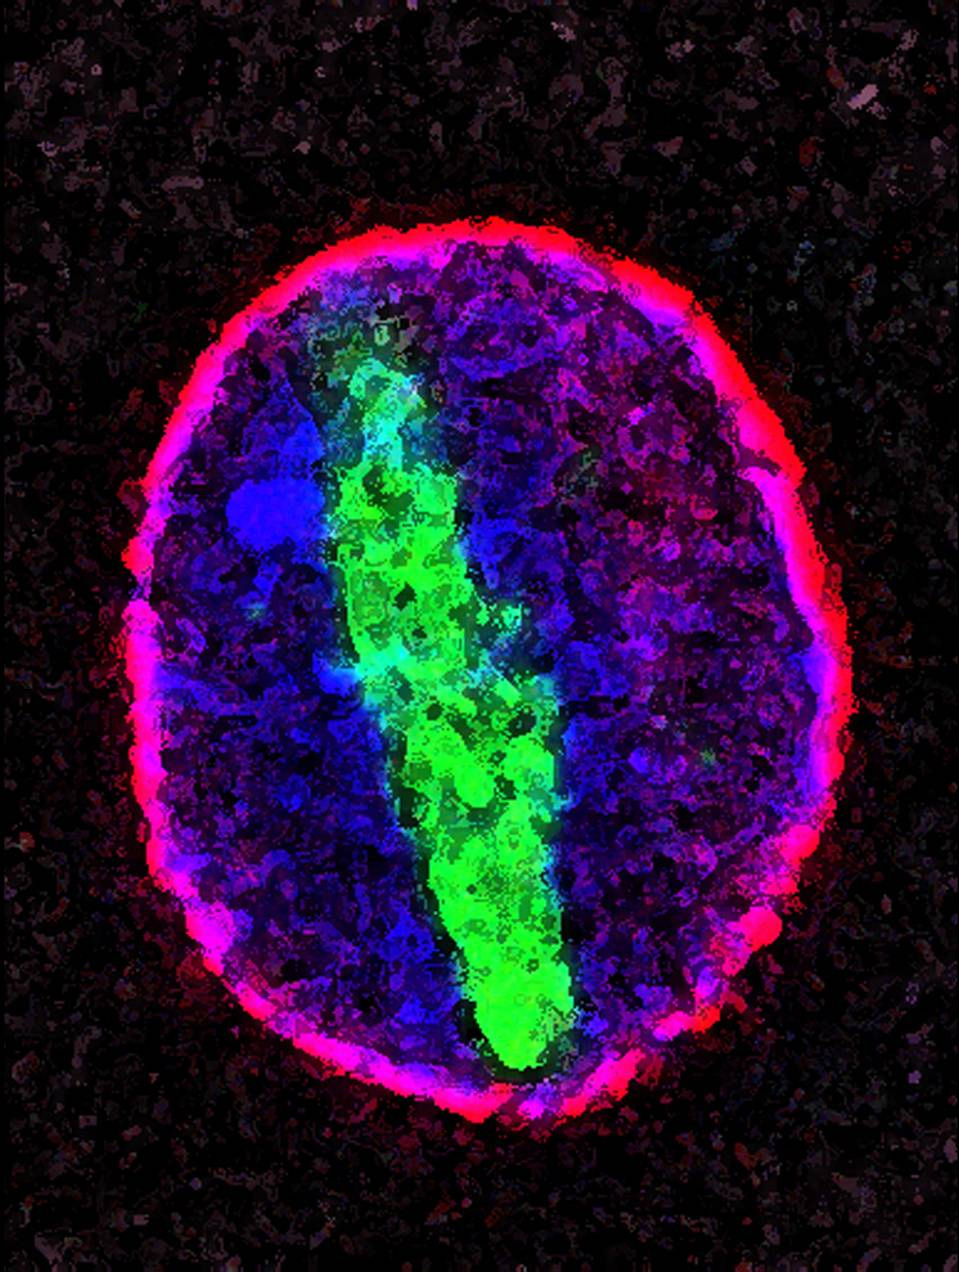

A protein called tubulin (green) accumulates in the center of a nucleus (outlined in pink) from an aging cell. Normally, this protein is kept out of the nucleus with the help of gatekeepers known as nuclear pore complexes. But NIGMS-funded researchers found that wear and tear to long-lived components of the complexes eventually lowers the gatekeepers' guard. As a result, cytoplasmic proteins like tubulin gain entry to the nucleus while proteins normally confined to the nucleus seep out. The work suggests that finding ways to stop the leakage could slow the cellular aging process and possibly lead to new therapies for age-related diseases.